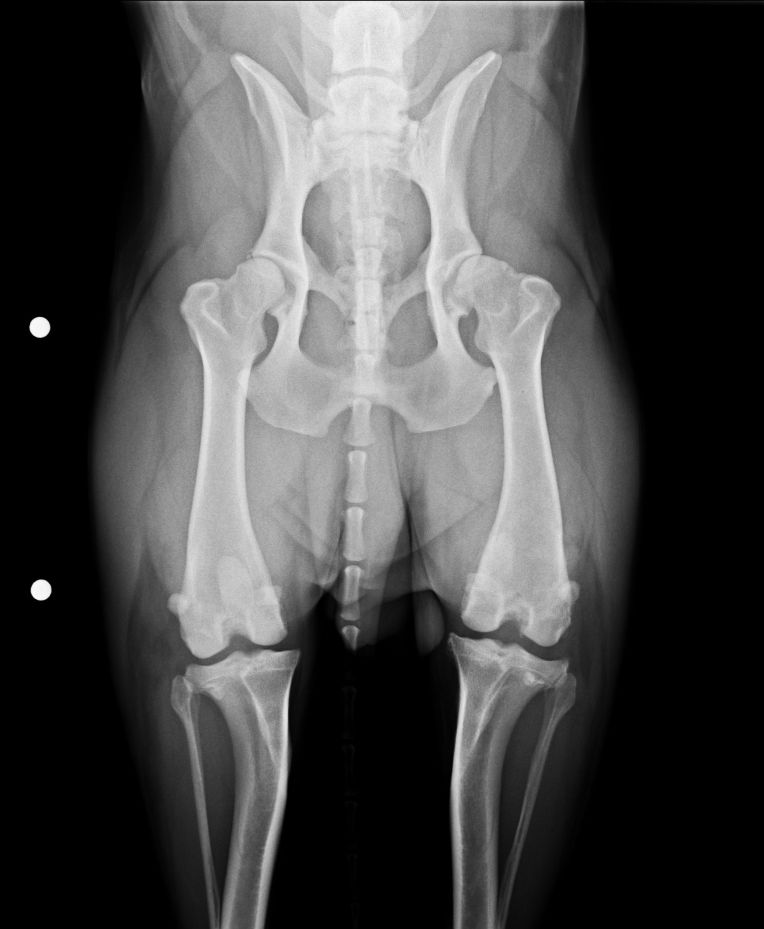

今回、右脚の前十字靭帯が断裂してしまいましたが、左側の脚も靭帯が伸びていて更に一部断裂していると診断されました。

更にERの検査では、左脚の膝蓋骨脱臼を確認。

大腿骨にある膝蓋骨が収まる滑車溝が浅いみたいで、脱臼しやすい骨の状態なんだそうです。

滑車溝が浅いのは恐らく生まれつきのモノで、前十字靭帯断裂も、これを庇っての事だったんじゃないかというのが、ERの見解。

↓ 楕円形に見えるのが膝蓋骨(膝のお皿)

左脚(写真右側)の膝蓋骨が滑車溝のところにない。